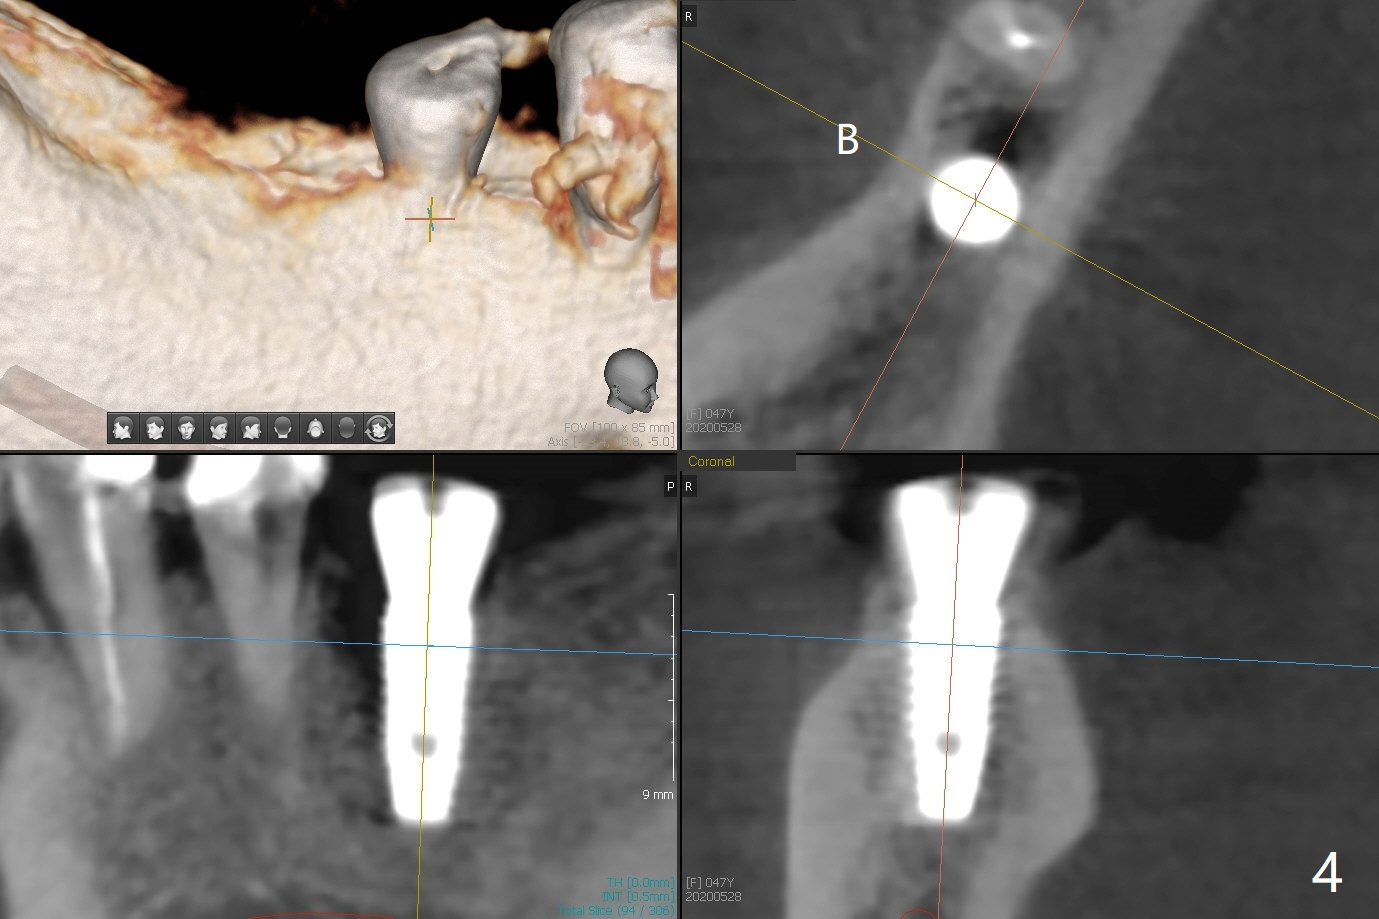

The female patient has limited mouth opening, complicated further by supraerupted opposing tooth. It is difficult to insert point drill and tap drill for #30 implant placement with guide. The former has to be inserted into the sleeve of the guide extraorally; two of them are placed intraorally together, while the tap drill is not used at all. When a 4.5x10 mm implant is placed, it is difficult to use #2 sensor to take PA. Finally a BW is taken with #2 sensor (Fig.1), while a PA is taken with #1 sensor (Fig.2). CT is taken to show clearance of the implant from the Inferior Alveolar Canal (Fig.3,4). To seat healing and later cemented abutments completely, a 5.5 mm profile drill is applied after implant placement; the outline is illustrated by red dashed line in Fig.1''. The elongated mesiolignual cusp of the tooth #3 has to be trimmed after placement of a 6x5 mm healing abutment. In fact trimming prior to osteotomy could solve the mouth opening partially. After removal of the 6x5 mm healing abutment, a 4.5x4(3) mm cemented abutment is incompletely seated (Fig.5 <) apparently due to proximity to the mesial crest (*). With reuse of a 4.6 mm profile drill, the abutment is fully seated (Fig.6), confirmed clinically by more clearance from the opposing tooth (Fig.7). Complete occlusal clearance is obtained by reduction of the opposing cusps without sensitivity since the tooth is nonvital (*). Return to No Deviation Xin Wei, DDS, PhD, MS 1st edition 05/28/2020, last revision 09/04/2020